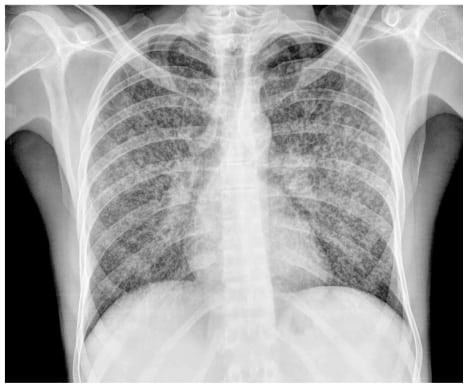

TAG: penyakit paru

Ada 35 Artikel yang mempunyai tag "Penyakit Paru"